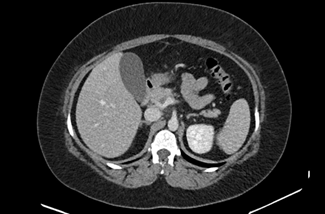

The initial physical examination showed a patient in discomfort but with normal vital signs. The abdominal palpation revealed epigastric tenderness without guarding or without other signs suggestive of acute abdomen. Surgical sites appeared to be well-healed, clean, and dry with no evidence of drainage or dehiscence. The laboratory analyses showed elevated inflammatory parameters (13,500 leukocytes and a C-reactive protein level of 123,20 mg/dL) and normal levels of amylase and lipase. A contrast-enhanced abdominopelvic computed tomography (CT) scan (Figures 1, 2, and 3) showed a dilatation in the mesenteric vessels, particularly the superior mesenteric vein, which had a luminal filling defect near its confluence with the splenic vein. The CT scan also revealed thickening of the adjacent adipose tissue, albeit without signs of intestinal ischemia. The patient was admitted to ward and started on LMWH 100 mg every 12 hours along with reinforced IV hydration. After three days in the hospital, she was discharge home asymptomatic. Anticoagulation therapy was continued with LMWH for one month before transitioning to a non-vitamin K antagonist oral anticoagulant (NOAC), specifically Apixaban 5 mg every 12 hours, and the use of estrogen for birth control was discontinued. At the three-month follow-up, the patient had lost 20 kg and was scheduled to repeat the CT scan and to discontinue anticoagulation therapy approximately six months after the thrombotic event.

Figure 3 CT scan showing densification of adjacent mesenteric adipose planes.